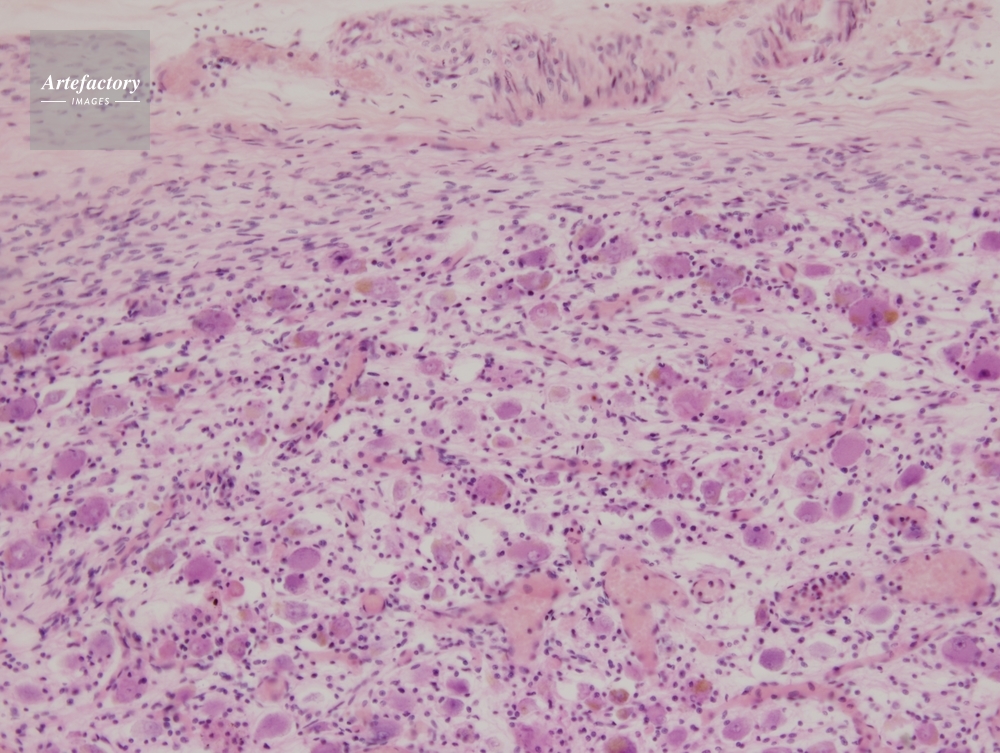

| 作品番号 | 03400159 | クレジット表記 | (c)OLYMPUS CORPORATION Technolab / Artefactory | |

| 作品タイトル | その他・不明 | モデルリリース | なし | |

| 作家 | OLYMPUS CORPORATION Technolab | プロパティリリース | なし | |